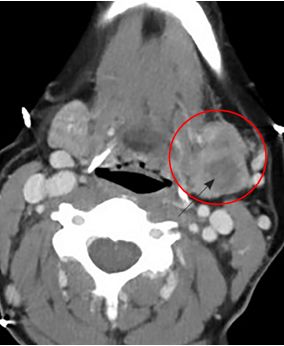

La TC o la RNM deben reservarse para los casos en que el diagnóstico de parotiditis recidivante ofrezca dudas, o ante la presencia de otros procesos patológicos, para los cuales son más confiables.

En primer lugar la ecografía que muestra un agrandamiento difuso de la glándula afectada, disminución global de la ecogenicidad con imágenes internas heterogéneas hipoecoicas de 2 a 4 mm de diámetro. El análisis histopatológico sugiere que estas áreas representan ductos periféricos dilatados con infiltración linfocítica. En un estudio realizado por Nozaki 1994, se vieron áreas hipoecoicas en todas las glándulas aumentadas de volumen y en algunas con volumen normal.